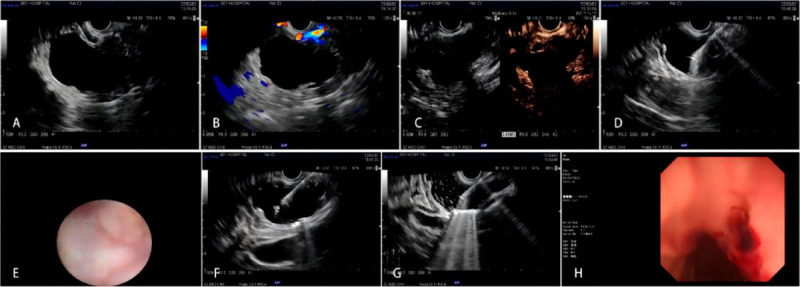

Objectives: To explore the safety and efficacy of injections of 1%, 2%, or 3% lauromacrogol during EUS-guided lauromacrogol ablation (EUS-LA) for the treatment of pancreatic cystic neoplasms (PCNs) and to determine the optimal concentration of lauromacrogol for use in EUS-LA therapeutic regimens.

Methods: From May 2021 to January 2023, patients who met the indications for EUS-LA were randomly divided into 3 groups: A, B, and C; the patients in these groups were injected with 1%, 2%, and 3% lauromacrogol during EUS-LA, respectively. Safety was evaluated based on the incidence of postoperative complications. Efficacy was comprehensively evaluated by assessing the ablation rate and ablation effect.

Results: Forty-two patients underwent EUS-LA, and 31 patients completed at least 1 postoperative re-examination. No acute pancreatitis was observed in the 1% and 2% lauromacrogol groups, and 1 case of acute pancreatitis occurred in the 3% lauromacrogol group. The total complication rate was 2.4%. The median ablation rates of the groups were 94.1%, 82.0%, and 100.0%, respectively. There were statistically significant differences in the EUS-LA ablation rate between the 1% and 3% lauromacrogol groups and between the 2% and 3% lauromacrogol groups. There was a statistically significant difference in complete disappearance between the 1% and 3% lauromacrogol groups as well as between the 2% and 3% lauromacrogol groups.

Conclusion: The short-term outcomes showed that injections of 1%, 2%, and 3% lauromacrogol were safe for use in EUS-LA, and injection of 3% lauromacrogol was the most effective for EUS-LA.